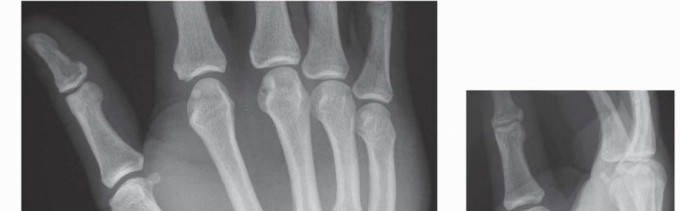

DEFINITION Fractures and dislocations of the carpometacarpal (CMC) joints of the index through small fingers …